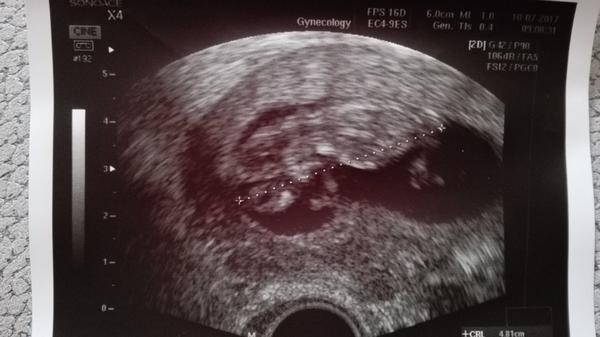

byla jsem na 4 ivf a mám jen jeden folikul,nikdy se mi to nestalo... ☹ vždy sem mela kolem 6-7 .zajímá mě stalo se to někomu z vás a je šance i s jednim..?

Fakt získali jen jeden jediný zraly oocyt? A transfer byl kolikaty den?